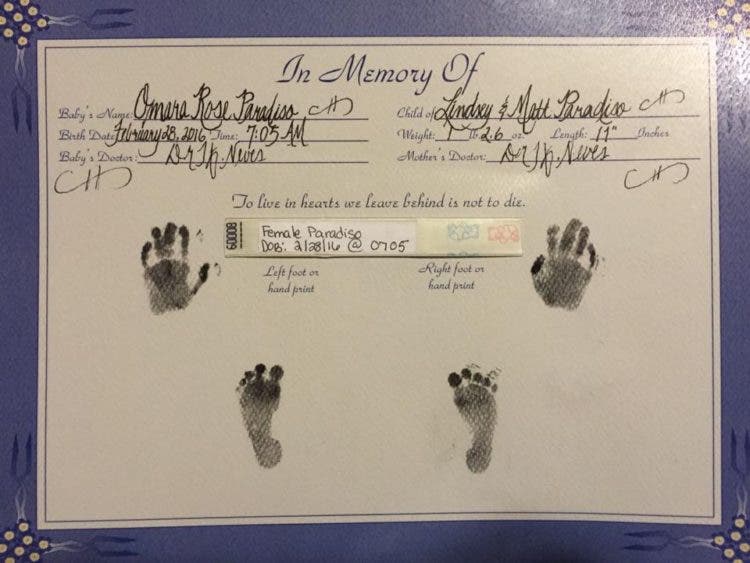

“Estuve en trabajo de parto durante 40 horas, fue muy doloroso y agotador pero quería dar a luz a mi hija para poder abrazarla y darle el último adiós”, contó Lindsey.

El 26 de febrero el pequeño corazón de Omara dejó de latir, dos días después entregaron el cuerpo a sus padres para darle el último adiós junto a sus familiares.